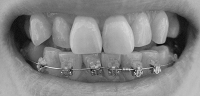

そんなわけで、ここんとこ変化がなくて寂しいので、この7ヶ月の変化が分かるように写真を並べて自分を励ますことにします~

ねね、全然違いますよね!!

正面から見たところなんて、こうやって見ると別人ですよね。